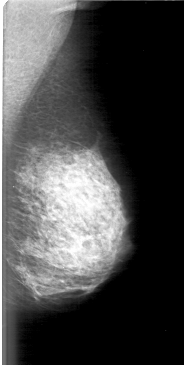

D_4079_1.LEFT_MLO

LEFT_MLO LINES 5101 PIXELS_PER_LINE 2566 BITS_PER_PIXEL 12 RESOLUTION 43.5 NON_OVERLAY

D_4079_1.LEFT_CC

LEFT_CC LINES 5296 PIXELS_PER_LINE 2491 BITS_PER_PIXEL 12 RESOLUTION 43.5 NON_OVERLAY